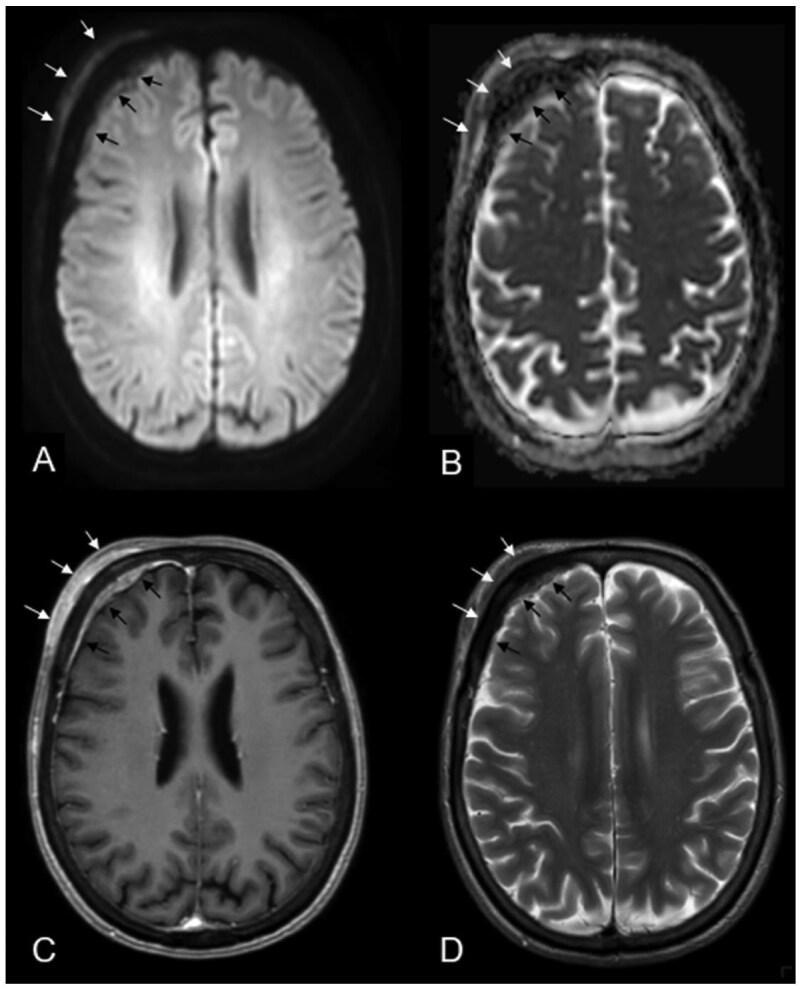

Primary central nervous system (CNS) mucosa-associated lymphoid tissue (MALT) lymphoma is a rare condition frequently mistaken for meningioma. Since these conditions require distinct treatment approaches, recognizing their imaging characteristics is essential for accurate clinical decision-making. A 69-year-old woman presented with headaches and forehead swelling, prompting MRI of the CNS. Suspecting an intracranial meningioma, the tumour board recommended surgical resection. However, histopathological analysis identified the lesion as a primary CNS MALT lymphoma. Follow-up revealed secondary cutaneous tumour infiltration, leading to a delay in adjuvant radiotherapy. Understanding the differential diagnoses of meningioma is critical for neuroradiologists and neurosurgeons to ensure appropriate treatment planning. This case highlights a misdiagnosis of meningioma that was ultimately identified as a primary CNS MALT lymphoma, emphasizing key imaging and clinical characteristics essential for distinguishing between the most important differential diagnoses of primary CNS MALT lymphoma.

摘要